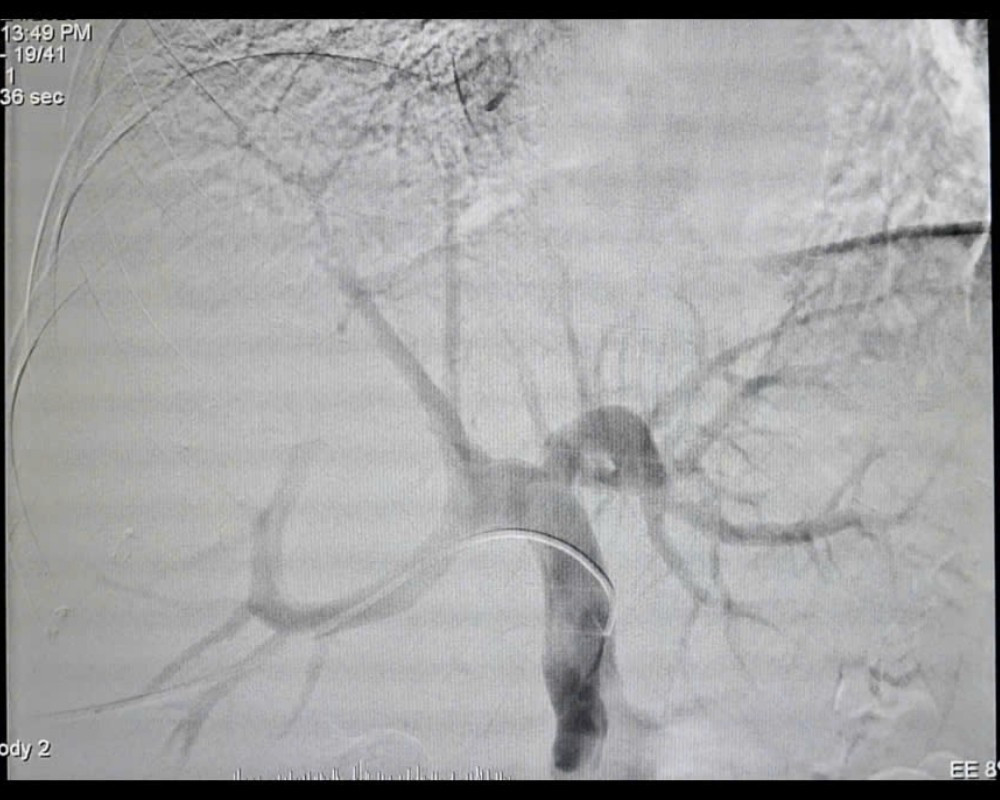

Quá trình can thiệp gây tắc tĩnh mạch cửa bên phải (PVE) - Ảnh BVCC

Trước tình huống này, các ê kíp chuyên môn đã hội chẩn liên khoa và quyết định thực hiện kỹ thuật can thiệp nút mạch gây tắc tĩnh mạch cửa bên phải (PVE). Thủ thuật này giúp chặn dòng máu nuôi phần gan phải có khối u và đồng thời thúc đẩy phần gan lành bên trái phát triển về thể tích. Chỉ sau 4 tuần, thể tích gan trái tăng lên 36,8% tổng thể tích gan, đủ điều kiện tiến hành phẫu thuật.

Ở giai đoạn đầu, phần gan giải phẫu chứa khối u sẽ được can thiệp nhằm giảm nguồn cấp máu thông qua các thủ thuật như chặn dòng máu tĩnh mạch cửa như tắc mạch (PVE), thắt mạch (PVL) để thúc đẩy phần gan lành còn lại phát triển khỏe mạnh (FLR).